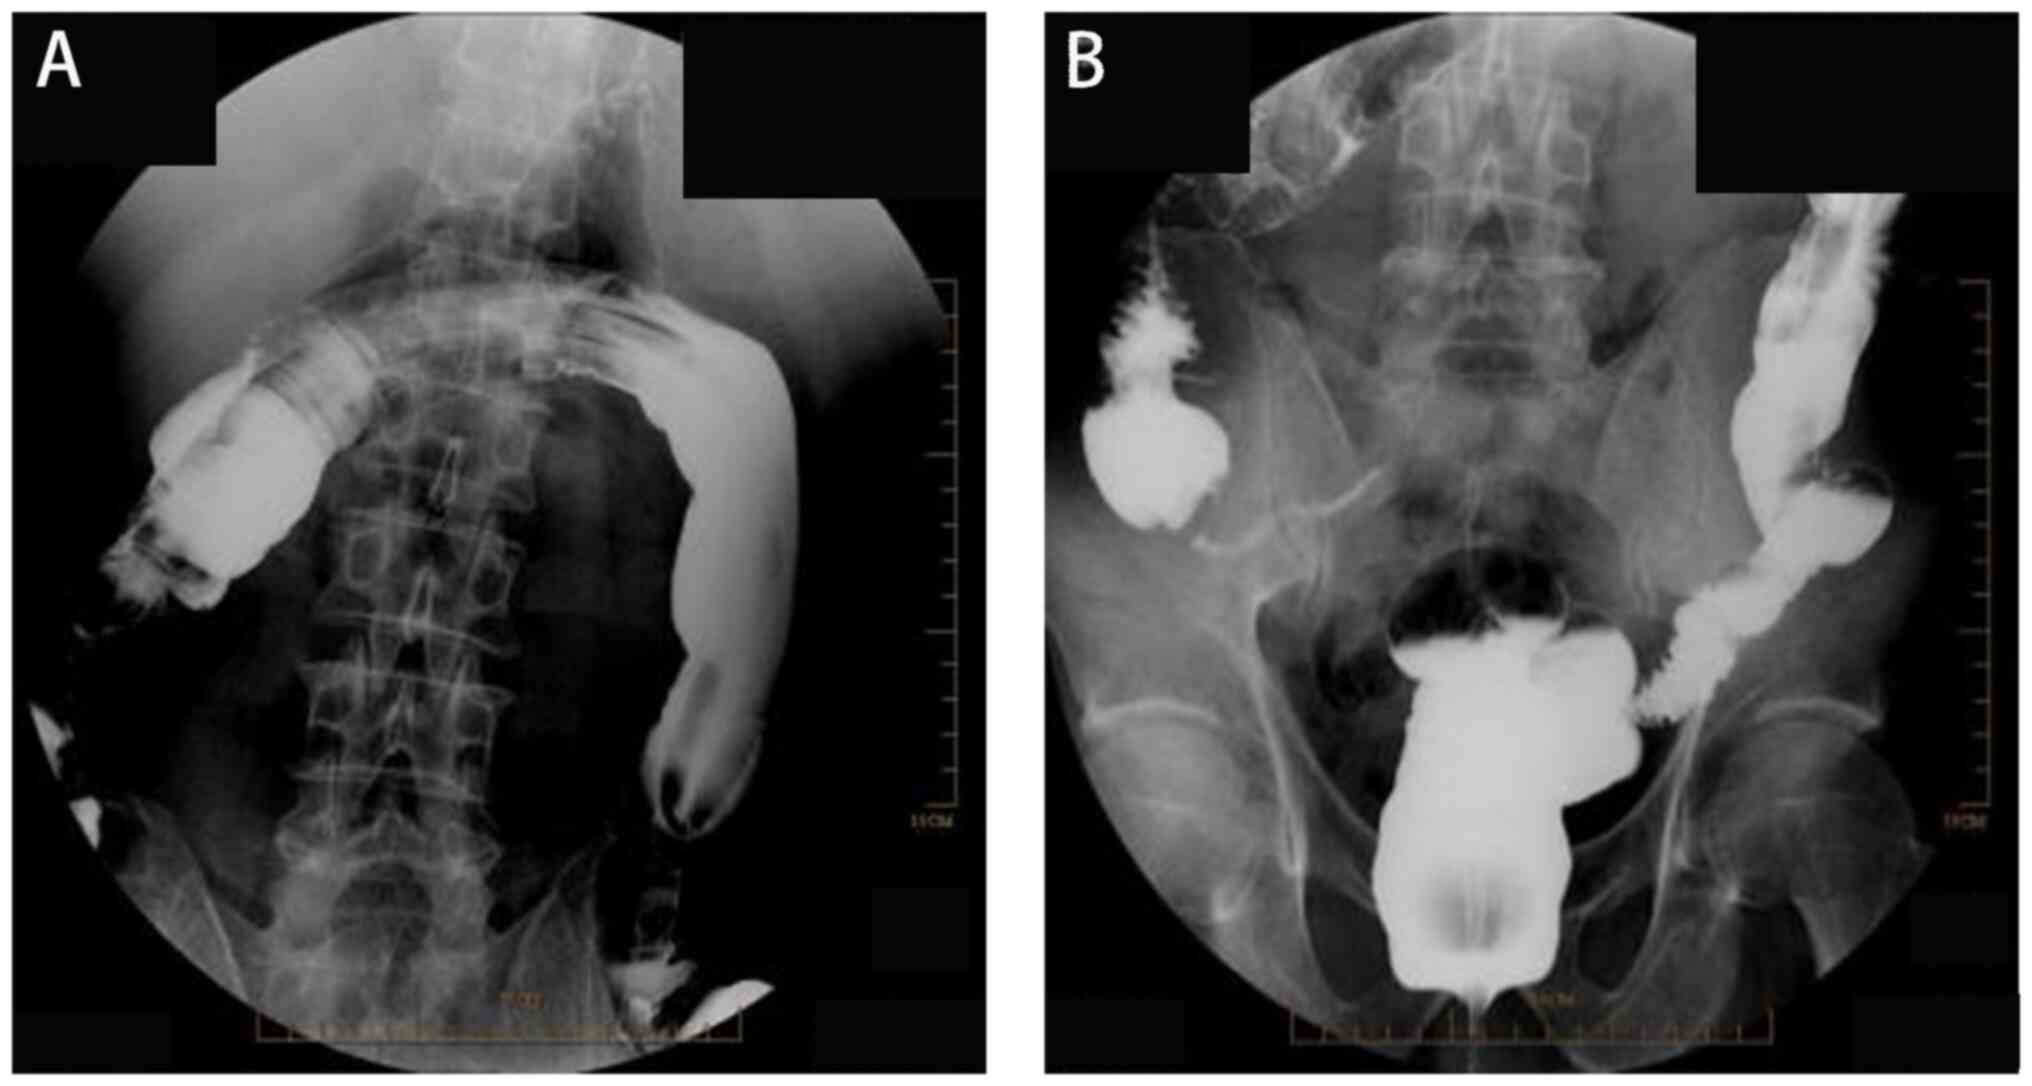

The fourth stage of treatment involved colonoscopy and removal of the colonic drainage stent. A total of 1 month after the healing of the colonic fistula, a retrograde colonoscopy of the anus showed no leakage of the contrast agent at the site of the colonic anastomosis fistula (Fig. 4). During colonoscopy, a drainage tube was identified ~40 cm from the anus. Using a ligation device, the colonic drainage stent tube inserted in the third stage was successfully removed.

Figure 4

Radiography contrast examination. No overflow of contrast agent was observed in the intestinal tract during radiography contrast examination. (A) Transverse colon. (B) Rectum.